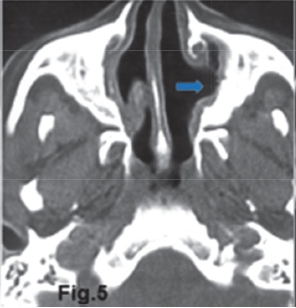

The intra-oral radiograph (Fig.1) shows a lesion at the apex of the 18. The lesion has extended to destroy a portion of the antral floor. There is also loss of the lamina dura and the presence of a "halo" (green arrow) of periosteal new bone suggestive of an osteitis. Some authors refer to this lesion as a localized mucositis or sinusitis of the left maxillary sinus. A Water's view of another patient (Fig. 2) shows an opaque right maxillary sinus and a classic air-fluid level (red arrow) in the left sinus, features which are consistent with acute sinusitis. Another example of acute sinusitis is discernible on the axial CT (Fig. 3) scan of another patient showing a clearly opacified left maxillary sinus with mucosal thickening and an air-fluid level (red arrow). Acute sinusitis presents clinically with facial pain, headaches, local tenderness and purulent discharge and is a common infection of the maxillary sinuses. Figure 4 is a Water's view of the maxillary sinuses showing a very sclerotic right sinus and small sclerotic maxillary antra in the left sinus (purple arrows), which is suggestive of chronic sinusitis. An axial CT scan (Fig. 5) of the same patient shows marked thickening of the walls of the right maxillary sinus with a thickened mucosa. The medial wall defects indicate that prior nasal antrostomies had been performed (blue arrow).

Chronic sinusitis is an infection of the sinuses that persists beyond the acute phase or fails to respond to treatment. Impaired sinus drainage is a predisposing factor. As in the acute form, chronic sinusitis is characterized by mucosal oedema and inflammation. With time, reactive sclerosis of the sinus walls and irreversible fibrosis of the sinus lining may develop. In another case in which the patient complained of nasal discharge and sinus pain an opportunistic infection, aspergillus sinusitis presented as a chronic sinusitis which did not improve with antibiotics or irrigation. In 90% of cases Aspergillus fumigates was the offending organism, as it was in this case. An axial CT (Fig. 6) scan of the affected patient shows thickened mucosa of the right maxillary sinus (yellow arrow) and the thickened walls of the left sinus, reflecting chronic sinusitis.